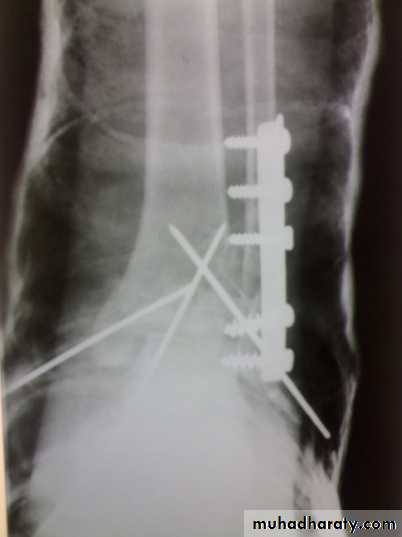

Zakho hospital Orthopedics Dr. MuthanaComminuted fractures of the tibial plafond (Pilon fracture)

Severe axial compression of the ankle (FFH).Shattering of ankle joint surface.

Swelling and blistering; treated by elevation and calcaneal traction.